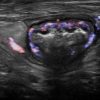

Viêm ruột

» Thông tin: Nữ giới – 55 tuổi.

» Lâm sàng: Tiêu chảy.